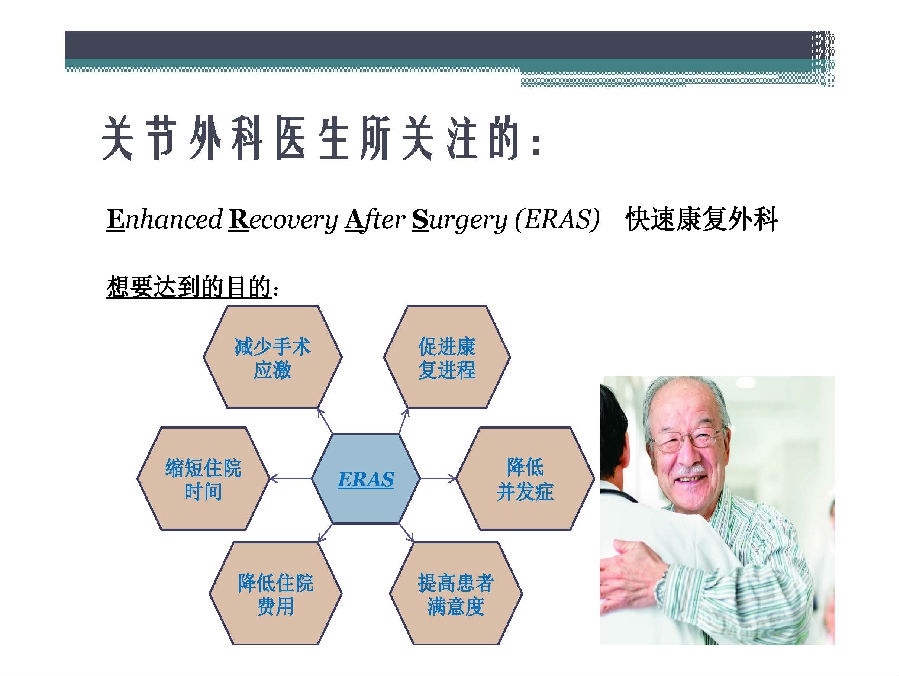

对于关节外科而言快速康复实际上是以病人加速舒适康复为目的,加强围术期的综合管理,包括疼痛和睡眠管理、血栓预防管理、感染预防管理、围术期血液管理,减少放置引流管、尿管、减少止血带应用,减少术后恶心呕吐,尽早进食,尽早康复等,逐步达到无血、无痛、无栓、无感、无肿、无管、无吐、无带等优良效果。为此,小编特邀王坤正教授等多位关节外科的专家参与撰写快速康复外科在关节外科的应用的主题文章,共话“人工关节置换快速康复”新理念,探讨建立符合我国特色的关节置换围手术期管理与快速康复体系,促进我国关节外科技术整体发展与提高。